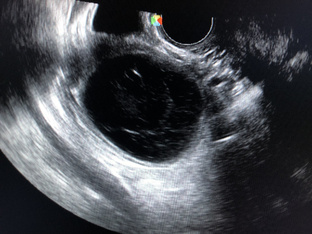

Собирались на ЭКО, а тут …

36 лет. Без детей. Две замершие на сроке 8 недель. Бесплодие несколько лет.  — Планировали эко. Начали обследоваться. И тут месячные что-то задержались. Ну, цикл и так не всегда регулярный, не обратила внимания. Но задержка уже 10 дней, и решила сделать тест. Вот.  Показывает фото. Контрольная полоска на тесте бледная.  Но точно не «призрак». Беременность.  Но может быть все что угодно. От малого срока нормальной до внематочной и замершей.  Мочевой тест не показатель.  Делаем УЗИ. Беременности нет...